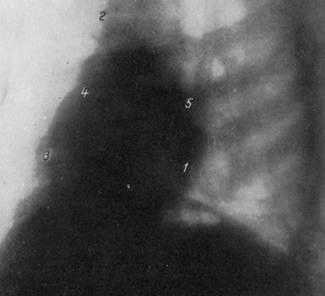

СХЕМА ПРОЕКЦИИ СЕРДЦА В ПЕРВОМ КОСОМ ПОЛОЖЕНИИ (поворот правым плечом к экрану на 45°).

1 —контур левого желудочка; 2 — контур аорты; 3 — правый желудочек; 4—контур правого предсердия; 5—контур левого предсердия; 6 — контур артериального конуса; 7 — ретрокардиальное пространство; 8 — ретростерналыюе пространство.

РЕНТГЕНОГРАММА НОРМАЛЬНОЙ ГРУДНОЙ КЛЕТКИ В ПЕРВОМ КОСОМ ПОЛОЖЕНИИ.

1 - дуга левого желудочка; 2 — аорта; 3 — дуга правого предсердия; 4 — дуга левого предсердия; 5 — дуга артериального конуса.